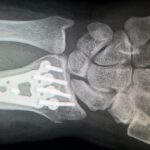

Diagnosis of the arthropathy component relies on a combination of clinical history, imaging, and supportive biochemical or genetic testing. Plain radiographs may demonstrate joint space narrowing, calcified cartilage or discs, osteophyte formation, and, in the spine, disc degeneration with calcification. Advanced imaging (such as MRI) may show cartilage damage and pigment deposition in connective tissues. Laboratory testing revealing elevated homogentisic acid in urine confirms the underlying metabolic disorder. Genetic testing may identify mutations in the relevant gene. A full assessment should include evaluation of other systemic complications (cardiac valves, kidneys, spine), given the systemic nature of the disease.